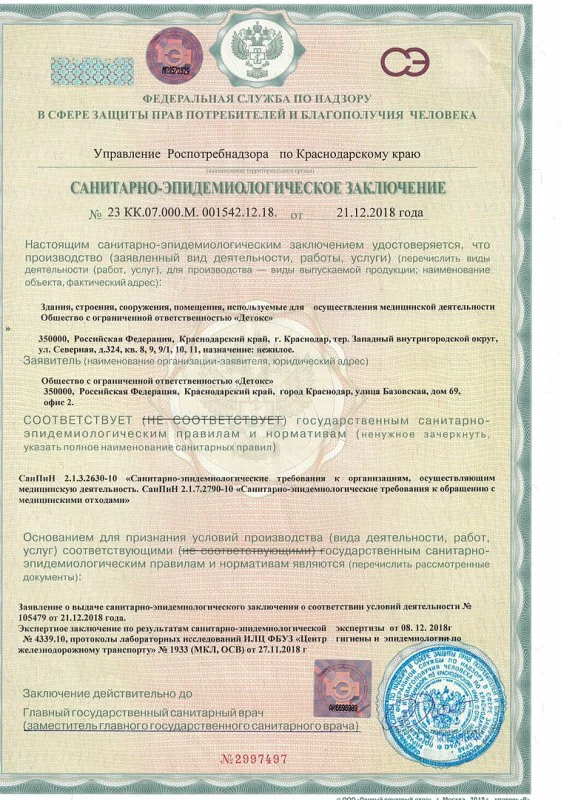

Лицензия на осуществление медицинской деятельности

Лицензия на осуществление медицинской деятельности

Лицензия на осуществление медицинской деятельности

Лицензия на осуществление медицинской деятельности

Лицензия на осуществление медицинской деятельности

Лицензия на осуществление медицинской деятельности

Лицензия на осуществление медицинской деятельности

Лицензия на осуществление медицинской деятельности